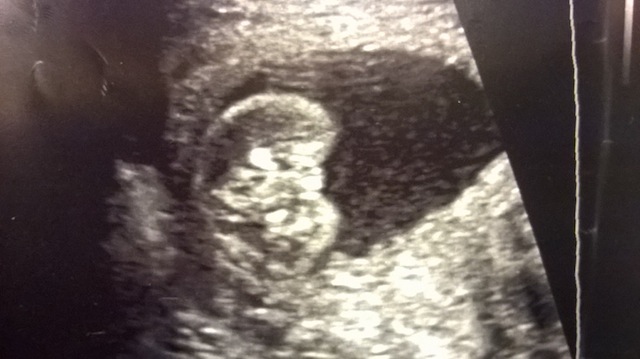

Now, today, my wife is 19 weeks. We went in for her anatomy scan of the baby, the tech got a shot of the genitals and she said based on what she sees, she thinks it's a girl because she said the lips of the labia are present in these pics below:

Attachment 19080

For those who might be confused about the "position" of the baby in those pics, it has its legs up in the air and you are seeing a closeup of the genital region.